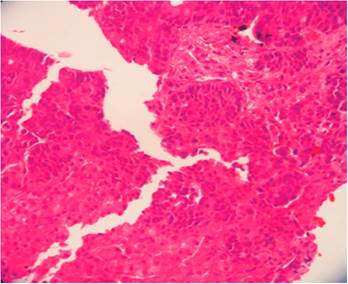

Se realizó una citología por aspiración con aguja fina (CAAF), que informó positividad para células neoplásicas: tumor epitelial de bajo grado tipo adenocarcinoma de posible origen endocrino. Se realizó laparoscopia y biopsia por trocar grueso, que informó las mismas características que la CAAF (Figuras 1 y 2). La tomografía axial computarizada (TAC) de abdomen, retroperitoneo, tórax y mediastino resultaron sin anormalidades.

La colonoscopia reveló una lesión de aspecto tumoral a nivel de la válvula ileocecal, redondeada de unos 4 cm de tamaño y del mismo color que la mucosa circundante; se apreció el signo de la tienda de campaña, que es la elevación de la pared intestinal con base ancha y vértice romo, sin pedículo con conservación de la mucosa intacta (Figuras 3 y 4). Se tomó una biopsia para el estudio histológico, que informó la presencia de un carcinoma neuroendocrino poco diferenciado grado III. La inmunohistoquímica fue positiva a enolasa neuroespecífica (NSE), sinaptofisina y Ki 67 (Figuras 5, 6 y 7).